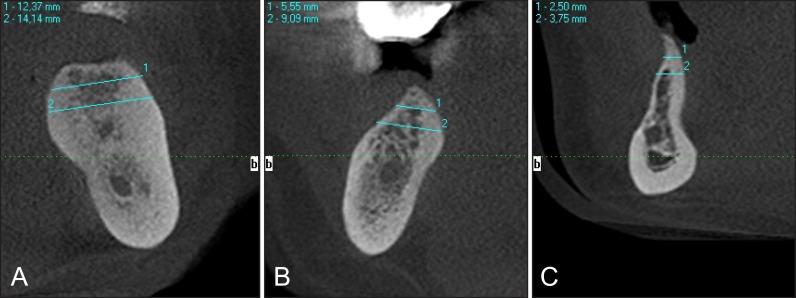

The purpose of present article was to review the classifications suggested for assessment of the jawbone anatomy, to evaluate the diagnostic possibilities of mandibular canal identification and risk of inferior alveolar nerve injury, aesthetic considerations in aesthetic zone, as well as to suggest new classification system of the jawbone anatomy in endosseous dental implant treatment.

In total 109 literature sources were obtained and reviewed. The classifications suggested for assessment of the jawbone anatomy, diagnostic possibilities of mandibular canal identification and risk of inferior alveolar nerve injury, aesthetic considerations in aesthetic zone were discussed. New classification system of the jawbone anatomy in endosseous dental implant treatment based on anatomical and radiologic findings and literature review results was suggested.

The classification system proposed here based on anatomical and radiological jawbone quantity and quality evaluation is a helpful tool for planning of treatment strategy and collaboration among specialists. Further clinical studies should be conducted for new classification validation and reliability evaluation.